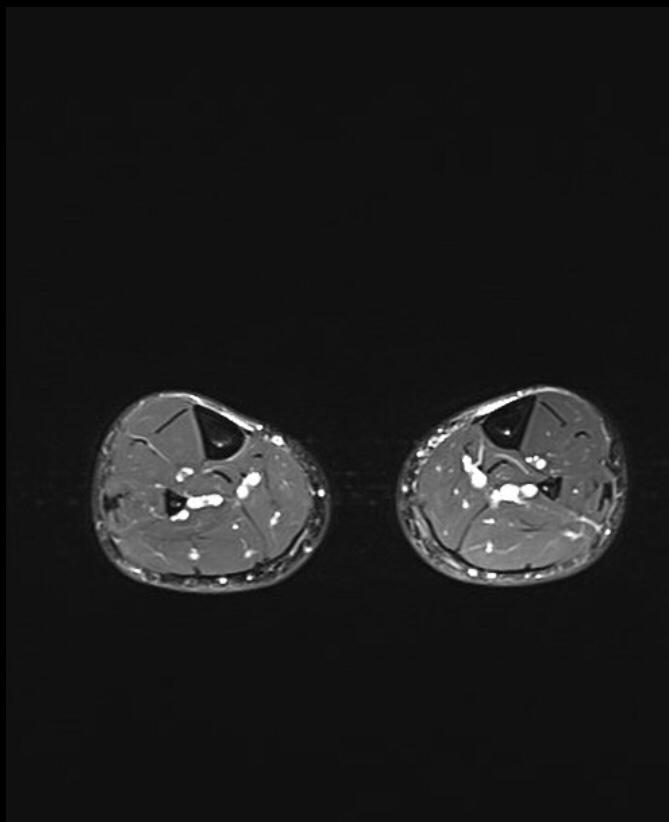

MRI is the most sensitive radiological examination (~88%). It may demonstrate a spectrum of findings ranging from normal to periosteal fluid to marrow edema to actual stress fracture. The medial cortex (+/- posterior cortex) is most commonly affected.